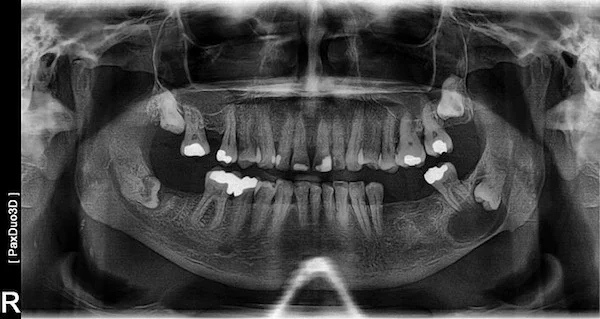

We utilize advanced digital imaging (OPG and 3D scans) to accurately locate the cyst, determine its size, and plan a safe surgical approach to remove it safely.